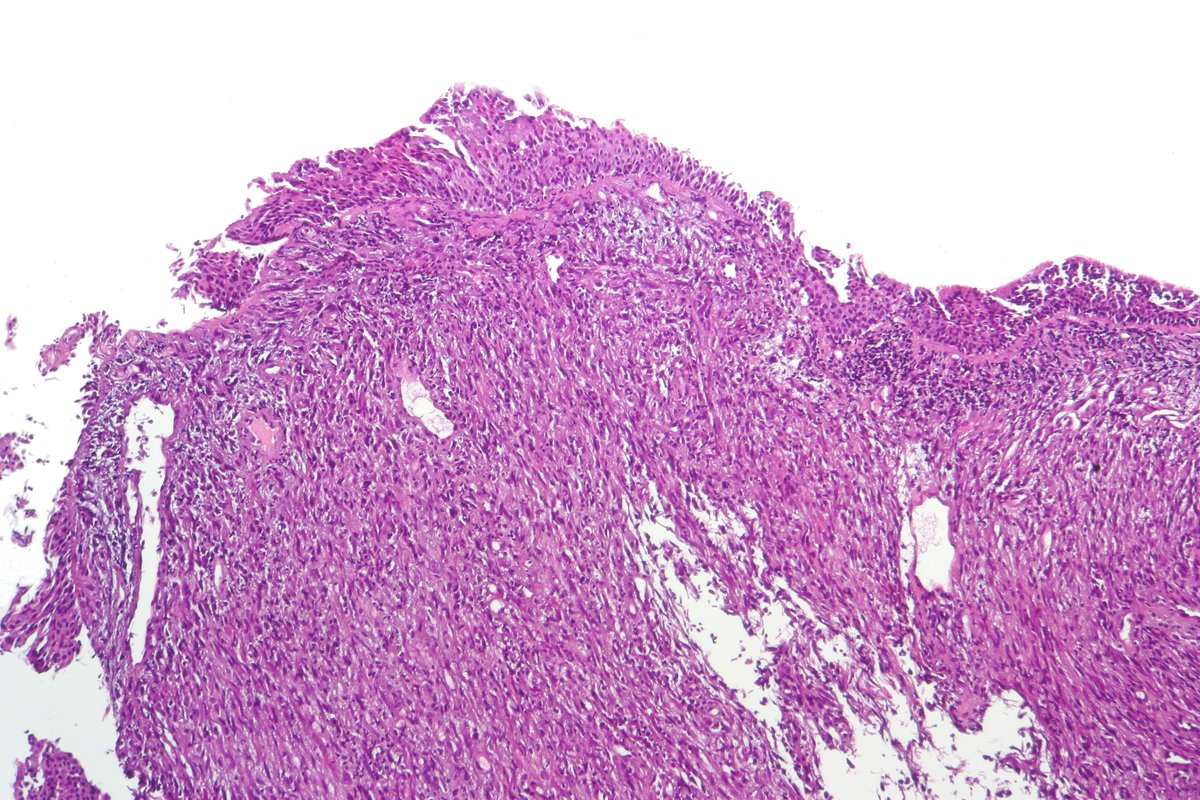

Atypical carcinoid of the lung exhibiting endobronchial growth, increased mitotic activity was seen (2-10 per 10 HPF). #pathology #PulmPath